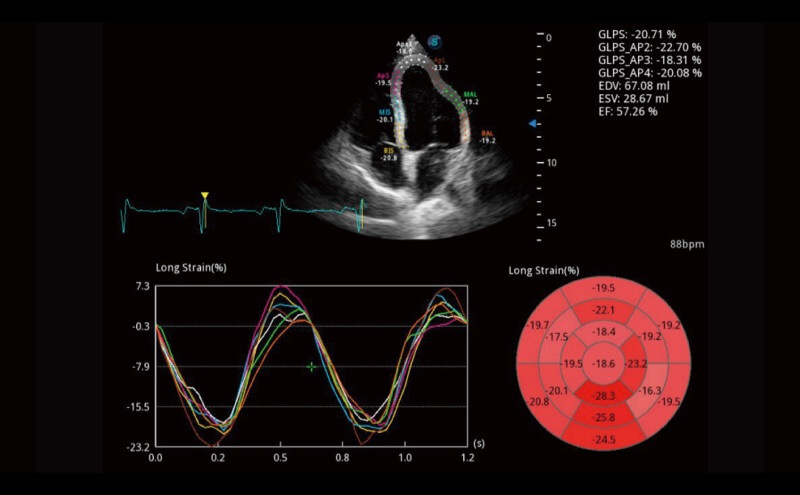

Ultraschall wird immer vielseitiger und übernimmt immer mehr klinische Aufgaben. Als Vorreiter, der Ärzten dabei hilft, mehr zu erreichen, ist ELITE mit einer umfassenden Palette fortschrittlicher Funktionen für die Allgemeine Bildgebung, Gynäkologie/Geburtshilfe, Kardiologie und mehr integriert.

Ultraschall wird immer vielseitiger und übernimmt immer mehr klinische Aufgaben. Als Vorreiter hilft ELITE den Ärzten dabei, mehr zu erreichen, indem es mit einer umfassenden Palette fortschrittlicher Funktionen ausgestattet ist, die die allgemeine Bildgebung, die Geburtshilfe/Gynäkologie, die Kardiologie und vieles mehr abdecken.